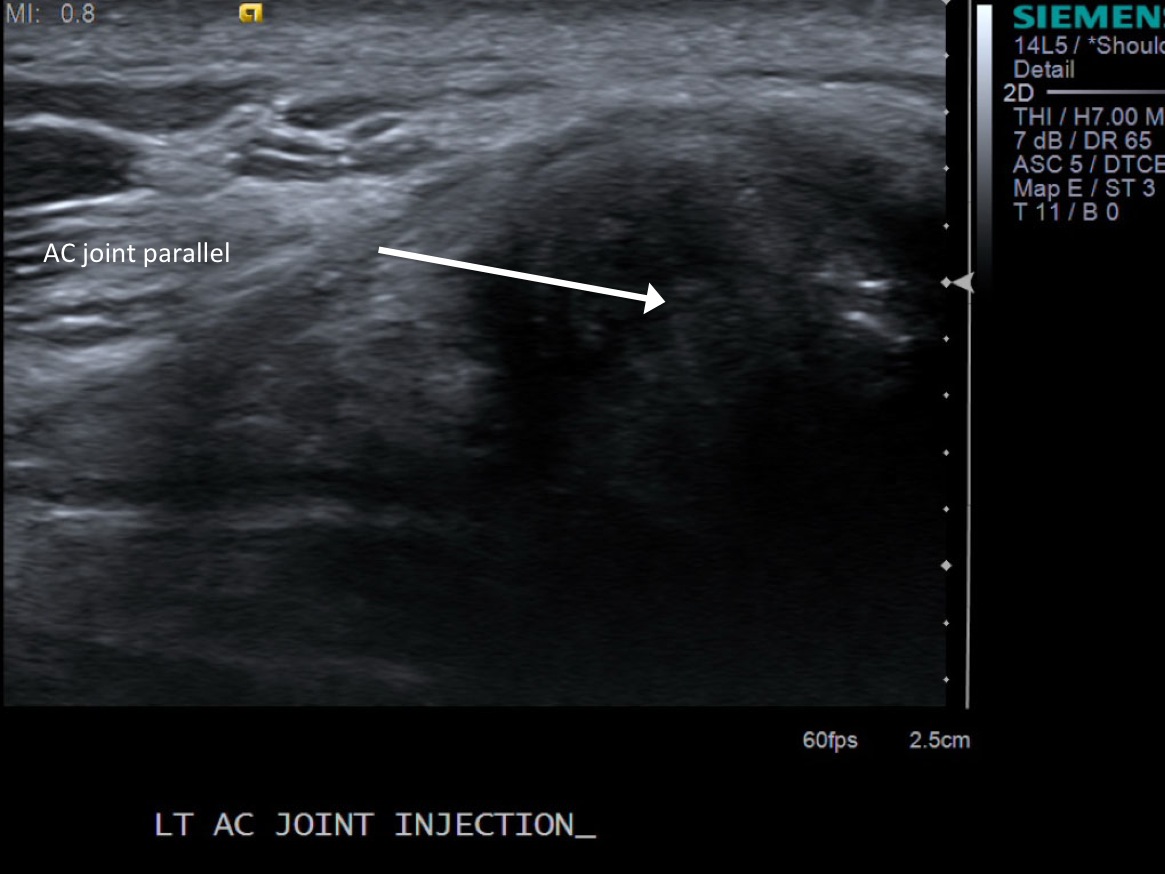

• probe: 14Mhz hockey stick probe

3. Place probe parallel to the joint and mark probe location and probable injection site